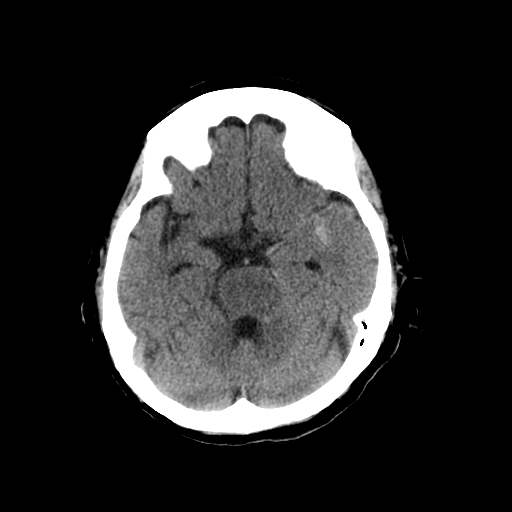

1-1. 高吸収領域の検出・表示例(下)

頭部CT検査において、周囲に比べ白く映る部分(高吸収領域)が見られる場合には、脳出血が疑われます。脳出血は高血圧・脳腫瘍・脳血管の異常などが要因となり、脳の動脈が破れて脳内部に出血した状態を指します。一方、周囲に比べ黒く映る部分(低吸収領域)が見られる場合には、脳梗塞が疑われます。脳梗塞は、脳内の血管が詰まるなどにより血液の流入が止まり、脳に酸素や栄養が行き渡らなくなる状態です。また、急性期の脳梗塞では、頭部CT検査において、灰白質と白質の境界が消失するなどの所見(ECS=early CT sign)が見られ(2)、こうした所見を見落とさずに治療につなげることが肝要です。